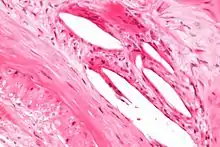

Micrograph showing the internal elastic lamina (thin pink wavy line - image edge mid-left to image edge bottom-centre-left). H&E stain.

The internal elastic lamina or internal elastic lamella is a layer of elastic tissue that forms the outermost part of the tunica intima of blood vessels. It separates tunica intima from tunica media.

It is readily visualized with light microscopy in sections of muscular arteries, where it is thick and prominent, and arterioles, where it is slightly less prominent and often incomplete.[1] It is very thin in veins and venules.[1] In elastic arteries such as the aorta, which have very regular elastic laminae between layers of smooth muscle cells in their tunica media, the internal elastic lamina is approximately the same thickness as the other elastic laminae that are normally present.[2]